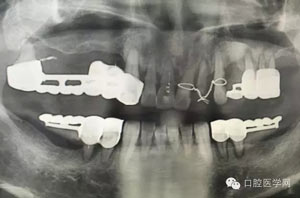

做根管的,都想做些難度大一點的,彎曲根管了、斷針了,可是臨床上很多時候是中等及以下難度的居多,我們要做的是盡我們所能做好這一部分,將我們力所能及的做好,而不是不切實際的幻想做一些我們條件設(shè)備不夠的病例。有些時候看到一些病例,很難想象是我們同行做的,我們是人,而不是神,我們也需要生活,我們追求效益沒有錯,我們給患者推薦好的材料,最終受益多的還是患者,這沒有錯,但是我們不是賣產(chǎn)品的,我們的本質(zhì)是醫(yī)療,不是流水線上的工人,將商品加工賣出去,我們所做的一切都是建立在符合修復(fù)設(shè)計原則的基礎(chǔ)上的,如若不符合,我們做的再美觀,再便宜,那又有什么意義呢?無論我們做什么樣子的修復(fù)體或者是治療,我們的標準是一致的,教科書上有明確的規(guī)定,我們這社會也有畸形,就拿簡單的冠修復(fù)來說,我們花費的精力是差不多的,我們需要的步驟是一樣的,但是價格差別那么大,是我們自己制定價格的問題,還是社會的問題?如若我們的冠的價格的制定差別不大,我們將更多的心思放到醫(yī)療本身上面,那么最終受益的還是患者,可是現(xiàn)在是顛倒的,我們成了產(chǎn)品的推銷者,整天想著怎么樣將價格高的冠賣給患者,而忽略了提高學習我們自身專業(yè)能力,我們整天想著怎么樣將環(huán)境打造的多么的好,然而材料上面卻是怎么樣的省怎么來,什么便宜用什么,裝修上面我們可以花很多,材料我們卻很摳,有時候我們材料買很好,可是我們卻束之高閣,很多時候我們講理念,講概念,可是我們卻很少腳踏實地的去做我們的專業(yè),只是用這些新鮮的名詞去和患者溝通。給大家看幾張不良的修復(fù)設(shè)計。